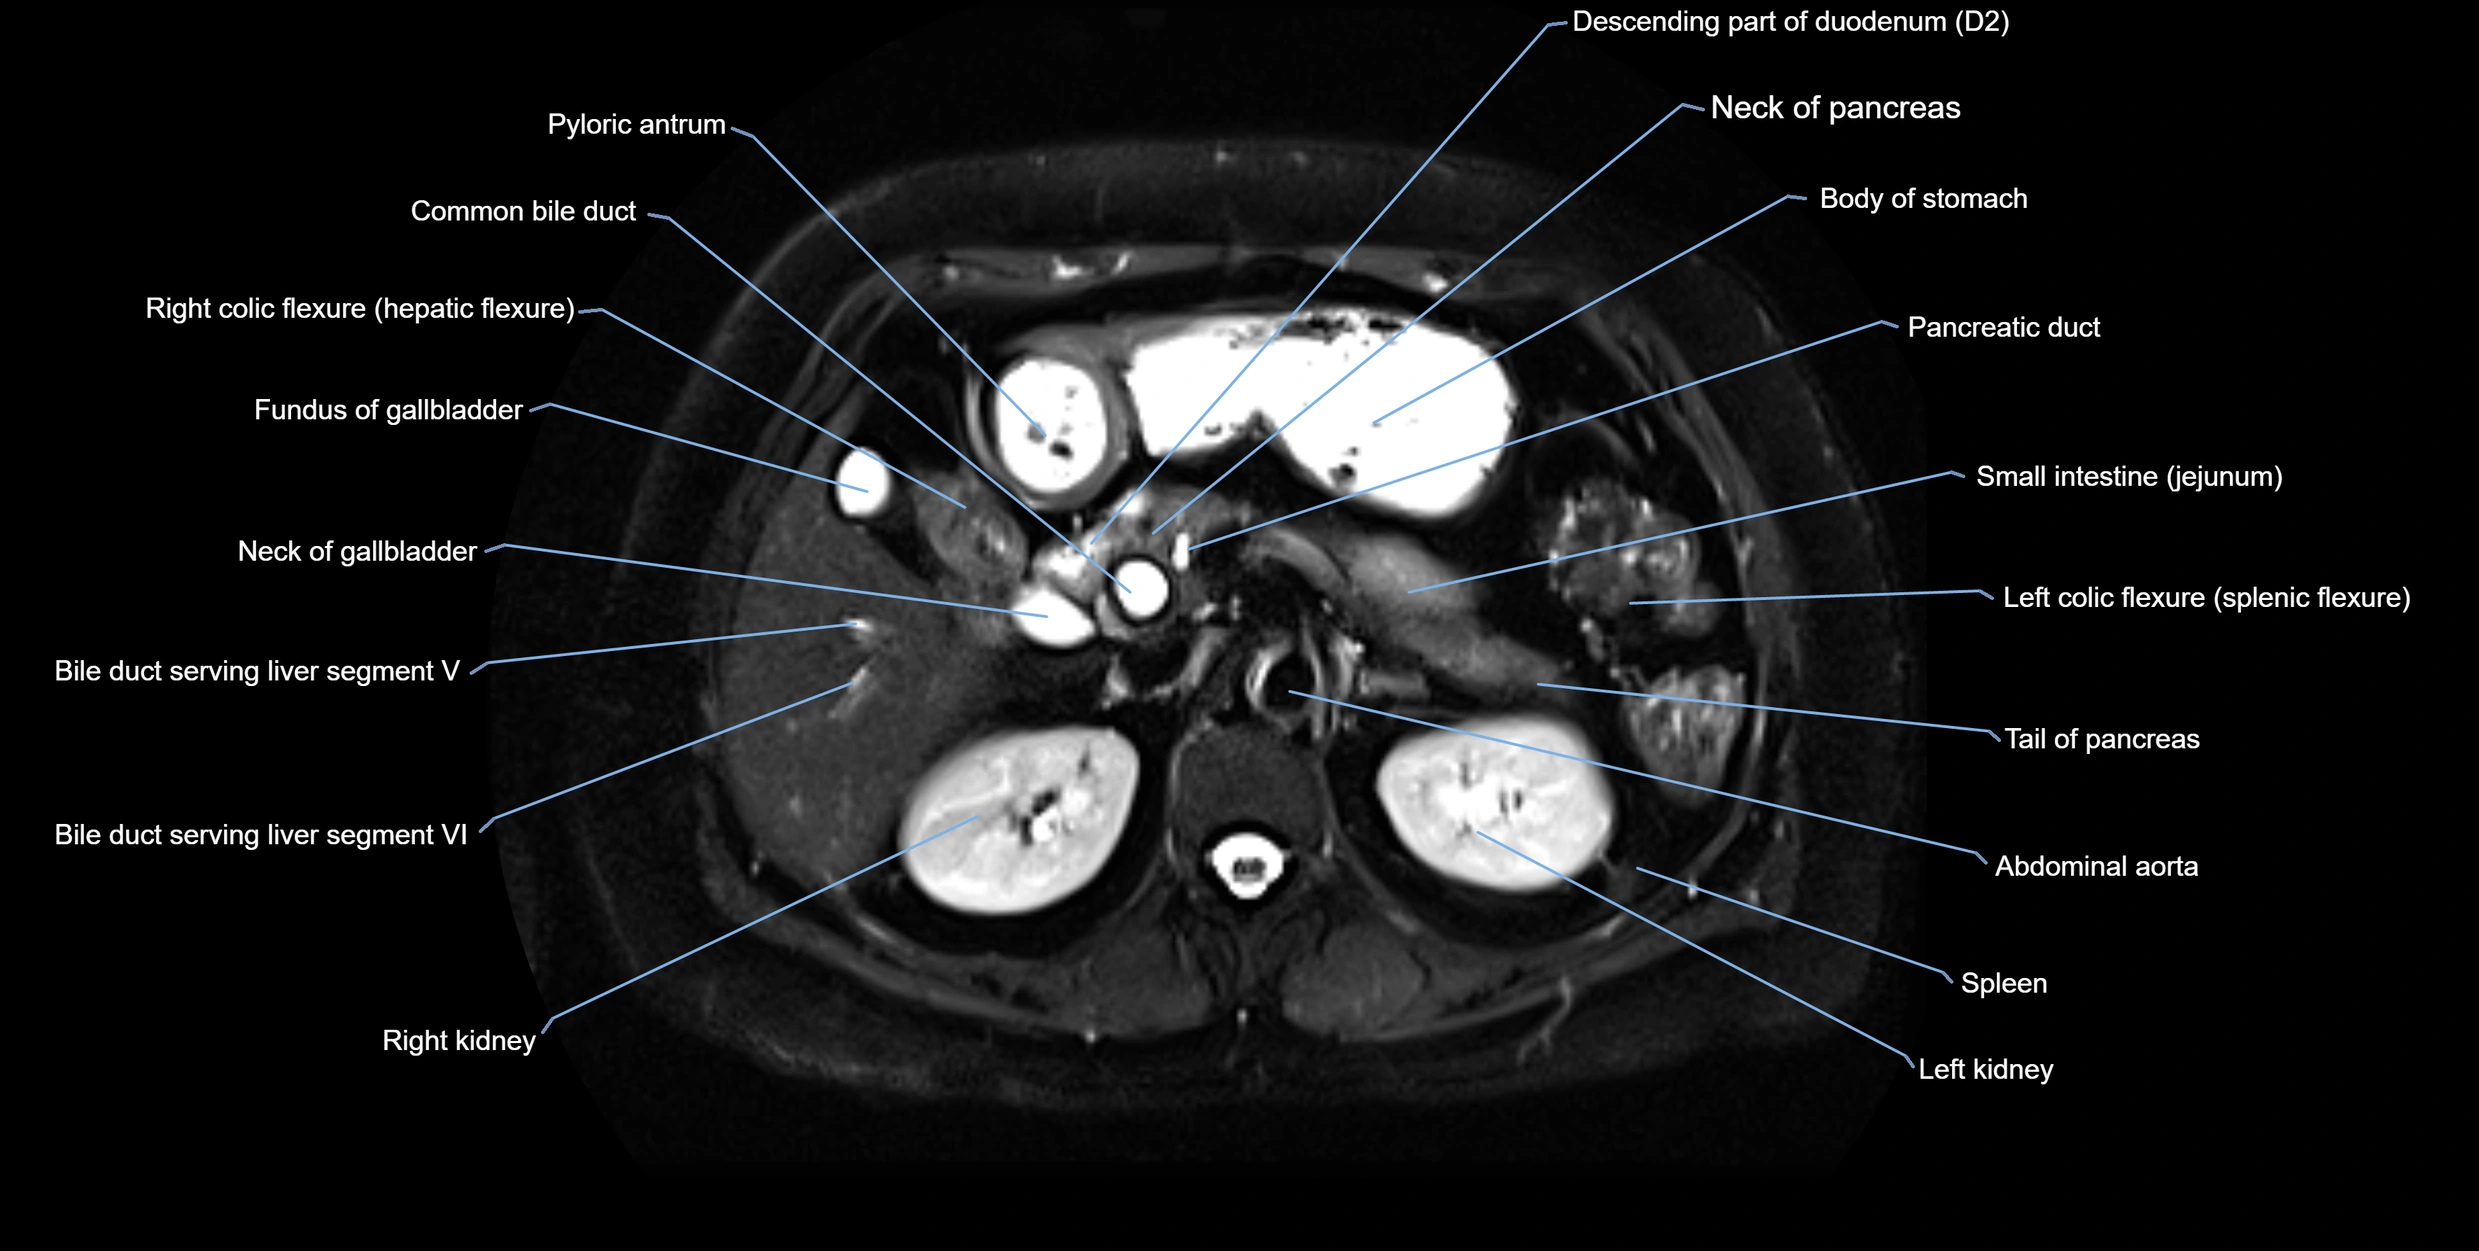

MRI Appearance

T1-weighted images:

• Not typically visualized unless dilated; appears as low signal tubular structure if seen

• Surrounding pancreatic parenchyma shows intermediate signal

T2-weighted images:

• Duct fluid appears bright

• Accessory duct seen as a fine high-signal tubular structure in pancreatic head

STIR (Short Tau Inversion Recovery):

• Duct fluid remains bright

• Surrounding fat suppressed, improving duct conspicuity

T1 Fat-Sat Post-Contrast:

• Normal duct does not enhance

• Surrounding inflammatory or neoplastic changes may enhance

T2 Fat-Saturated HASTE (single-shot):

• Accessory duct: bright, thin linear structure in pancreatic head

• Stones, strictures, or air bubbles appear as dark filling defects

• Excellent for rapid evaluation of duct patency

T2 TSE Fat-Saturated 3D (MRCP sequence):

• Duct visualized as a continuous bright tubular structure joining or parallel to the main pancreatic duct

• Allows 3D reconstruction of ductal anatomy and variants

• Excellent for diagnosis of pancreas divisum

Thick-slab T2 Fat-Saturated HASTE:

• Shows the accessory duct as part of the biliary–pancreatic system in a projectional image

• Highlights communication with main pancreatic duct and opening into the minor papilla

• Filling defects (stones, strictures) seen as dark spots within bright fluid

MRI image

image

Fullscreen Image